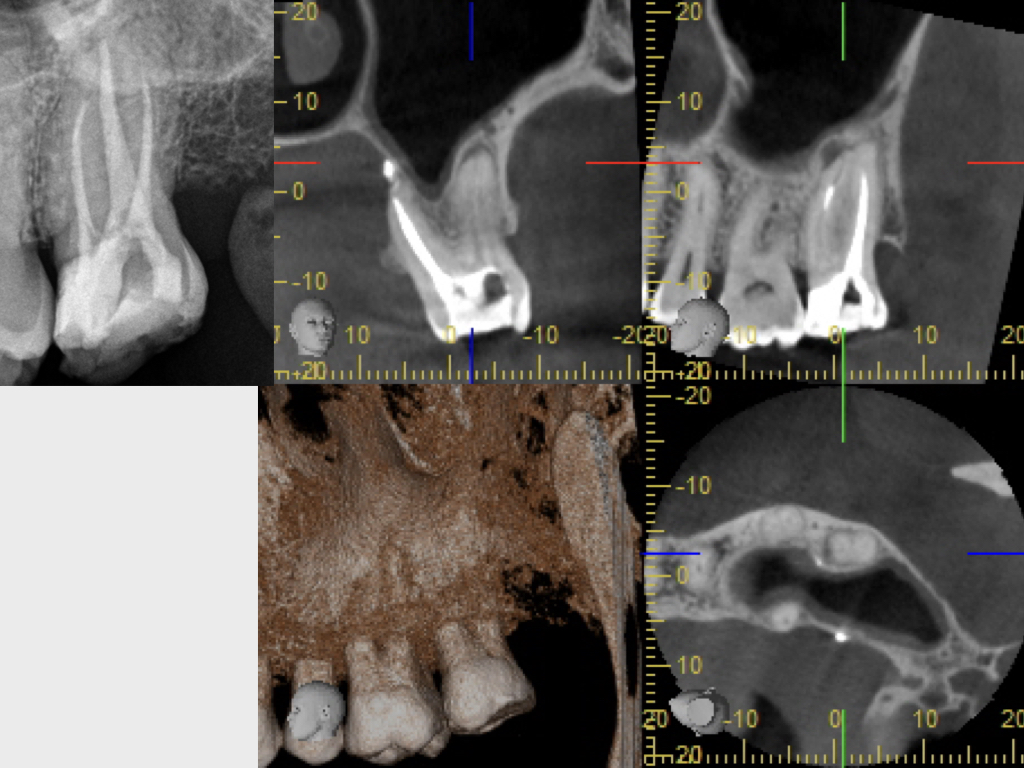

WSPick1.004

1024 × 768

Pick, Pick (1)